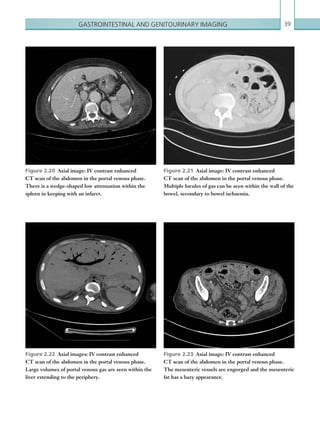

Figures 1.12a–c  Axial images: IV contrast enhanced

CT scans of the thorax in the arterial phase. Peripheral,

wedge-shaped area of consolidation shown. Over time,

the area of consolidation develops an irregular, thick

rind with areas of cavitation centrally due to infarction.

Note the associated pulmonary arterial filling defects in

1.12b and 1.12c consistent with pulmonary emboli.

narrowing due to recanalisation (Figures 1.14). A focal

linear intraluminal filling defect within a pulmonary

artery is suggestive of an arterial web, which can be seen

as a result of chronic emboli. Secondary pulmonary

artery hypertension can result from multiple chronic

emboli. The main sign of pulmonary hypertension

on CT is enlargement of the main pulmonary artery

(greater than 34 mm or larger than the corresponding

ascendingaorta;Figure 1.15).Mosaicattenuationofthe

lung parenchyma can also be seen in cases of chronic

pulmonary emboli, although this appearance has a wide

differential diagnosis (Figure 1.16).